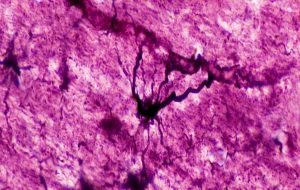

Strange ‘Hybrid’ Brain Cells Have Been Discovered Hiding Inside Our Heads An international team of scientists has found a whole